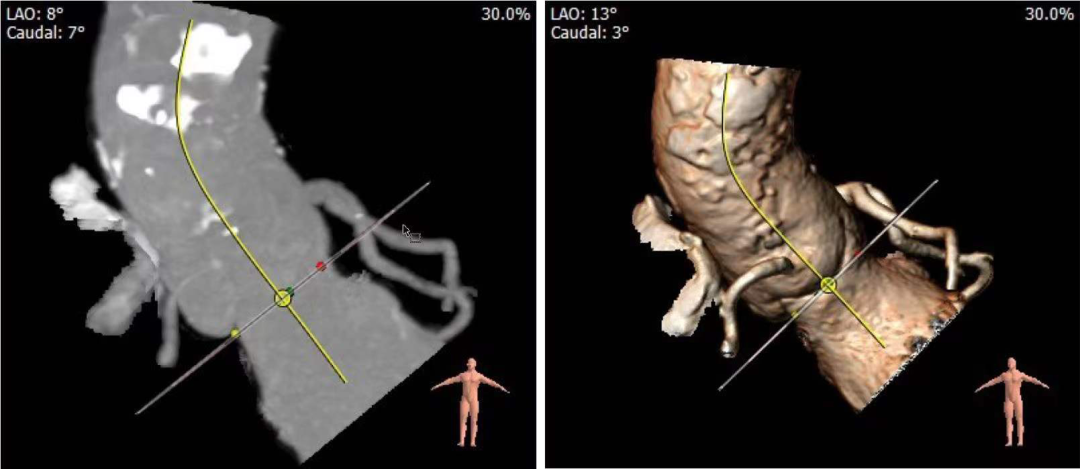

4.患者术中造影角度LAO:13°,CAU:3°;

投照角度:LAO13°CAU3°